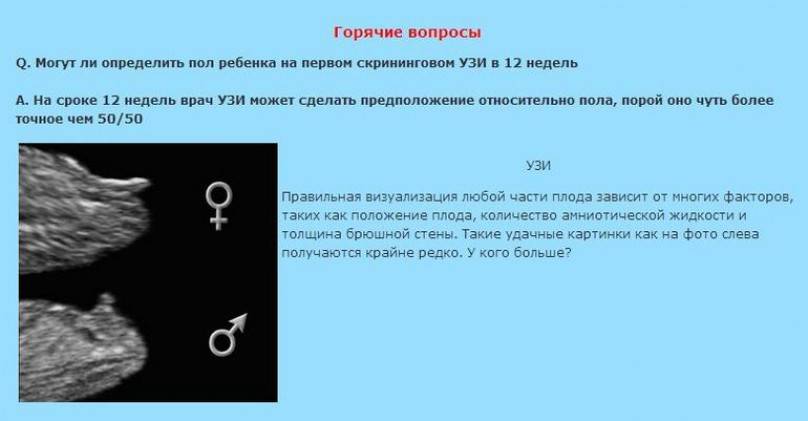

Пол на 14 неделе беременности по узи

Пол на 14 неделе беременности по узи 88 фото